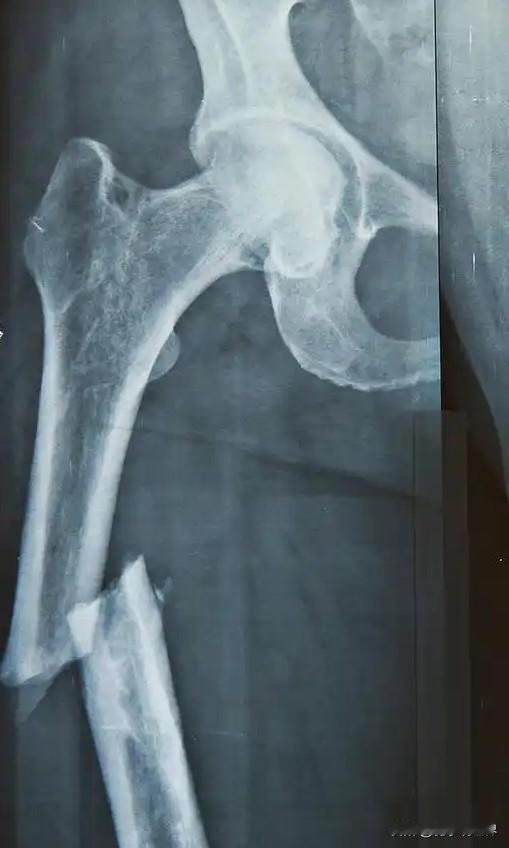

骨折后喝大骨汤到底好不好?要注意哪些膳食营养? 骨折是不少人碰到过或经历过的事情,同样是股骨的骨折或其它同一部位的骨折,有的人愈合的快,有的人则愈合的慢。影响骨折愈合的原因除了医疗技术水平差异和患者有无基础性疾病(高血压、冠心病、糖尿病等)之外,最主要原因还包括年龄和膳食营养的影响。儿童的骨骼愈合能力比较强,愈合的速度要比成人快得多,随着年龄增长,组织的再生能力就会逐渐减弱,因此老年人骨折愈合时间更长,风险也更高。 影响骨折愈合的膳食营养因素主要是缺乏蛋白质、钙、维生素D和维生素C等关键营养素。在我国很多地区,大家都相信骨折后,通过加强膳食营养(进补),可以加快骨折后的愈合,“吃什么补什么”的习俗非常盛行,这和中医的“以形补形”是一个道理,不少人通过熬大骨汤来进补,事实上骨头汤里主要是含脂肪和嘌呤,溶解到汤里的钙质很少,所以即喝汤又吃肉才叫好,营养成分主要还是在肉里,闽南地区有“七分肉三分汤”的说法,就是这个道理。钙是骨骼强化的核心矿物质,主要沉积在胶原框架上使其变硬,奶制品(牛奶、酸奶、奶酪)中含量比较高。胶原蛋白是骨基质的主要成分,合成胶原蛋白需要充足的蛋白质,所以补充胶原蛋白可以促进骨折的愈合,胶原蛋白主要来源于瘦肉(鸡肉、鱼肉)、鸡蛋、牛奶、豆制品、坚果等。补充适量的维生素D,主要是为了促进肠道对钙的吸收,是钙能利用的关键,多脂鱼(三文鱼、金枪鱼)或蛋黄中的维生素D含量比较高,另外晒太阳是必须的,是获取维生素D最主要、最有效的方式。维生素C则是合成胶原蛋白必不可少的催化剂,同时具有抗氧化作用,增强免疫力,柑橘类水果(橙子、柚子)、草莓、猕猴桃、西兰花、西红柿等食物中含量较高。要想骨折后愈合快一点,除了进补以外,一些不利因素也应排除,比如控烟、戒酒,香烟中的尼古丁会收缩血管,影响骨折部位的血液供应,导致缺氧和营养供应不足,过量饮酒则会干扰成骨细胞的功能,影响骨折的愈合。对于大多数人来说,通过均衡膳食一般都能满足营养的需要,如果通过检查发现确实存在某些方面摄入不足,需在医生指导下进行补充(钙剂和维生素D),不要盲目进补。